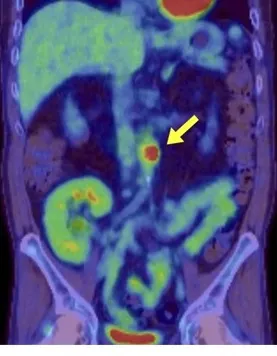

Uma causa incomum de hematúria glomerular intermitente!

Uma causa incomum de hematúria glomerular intermitente!